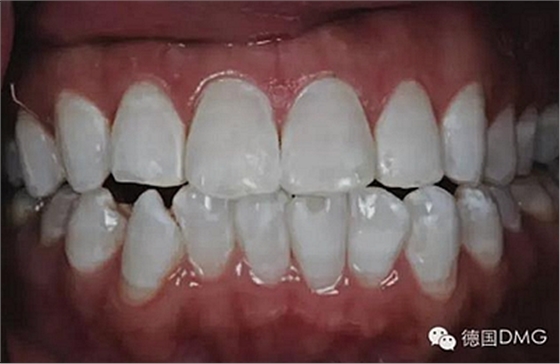

5、由于氟斑牙存在釉質(zhì)礦化不全等問題,家庭漂白兩周后,使用標(biāo)準(zhǔn)的樹脂滲透技術(shù) (Icon, DMG Products, Hamburg. Germany) 來預(yù)防釉質(zhì)齲。最后,徹底改變患者的前牙美學(xué),并在一年后仍保持穩(wěn)定。

利用釉質(zhì)打磨技術(shù)聯(lián)合牙齒漂白和樹脂滲透技術(shù)的微創(chuàng)方法是治療重度氟斑牙的有效方式。同時(shí),這一技術(shù)費(fèi)用低、省時(shí)間。